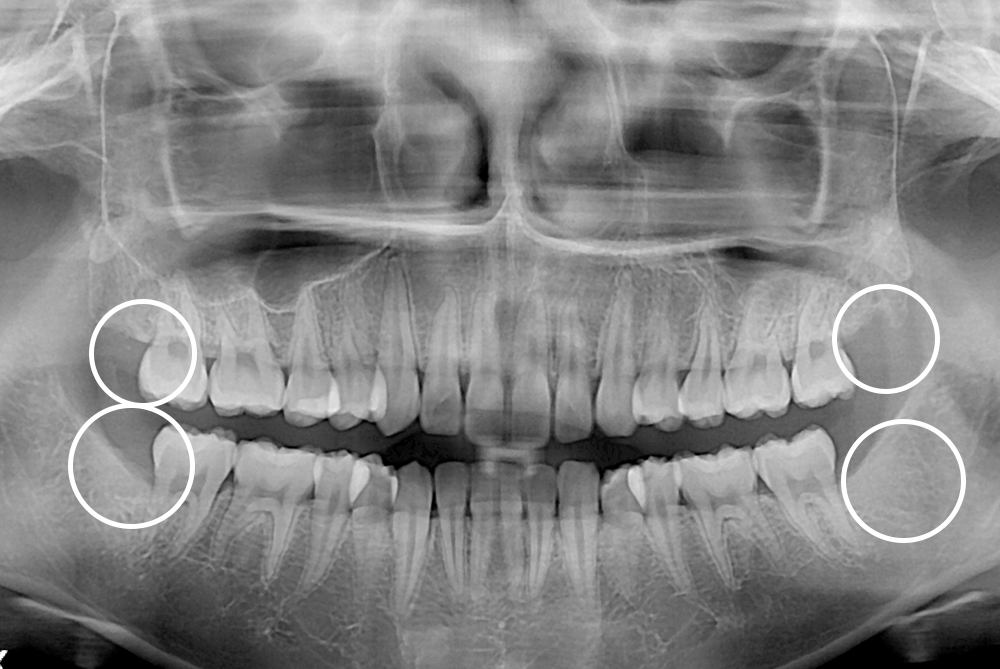

[사랑니] 매복 사랑니 발치

치료전 : 2020-04-04